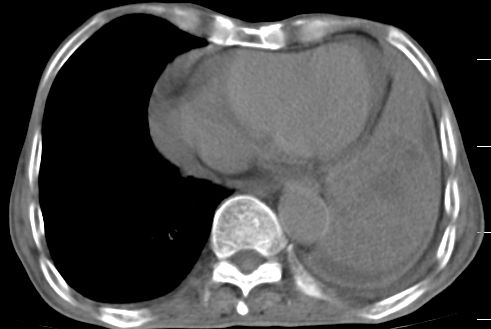

标题: CT10141:男、84岁,咳嗽、咯血1年。 [打印本页]

标题: CT10141:男、84岁,咳嗽、咯血1年。

支持左侧中央型肺癌伴下叶肺不张\\纵隔淋巴结转移.左侧包裹性胸腔积液\\心包积液.左侧少量胸腔积液..慢性支气管炎伴部分间质纤维化.

支持:左侧中央型肺癌伴下叶肺不张\\纵隔淋巴结转移.左侧包裹性胸腔积液\\心包积液.左侧少量胸腔积液..慢性支气管炎伴部分间质纤维化.另:支气管分支根部明显阻塞 狭窄,内膜凸凹不平,提示内膜增生物。

咯血病史较长,左肺下叶实变,体积未明显缩小,隐约可见血管影及坏死阴影,双肺门及纵隔淋巴结增大,心包增厚积液,纵隔右移位,单侧胸腔积液,首先考虑:大叶型肺泡癌伴纵隔心包转移。